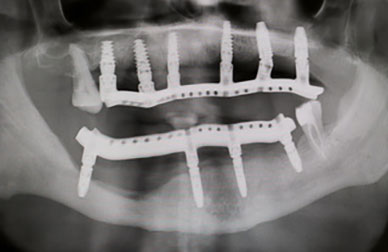

Carga inmediata

Implantología avanzada